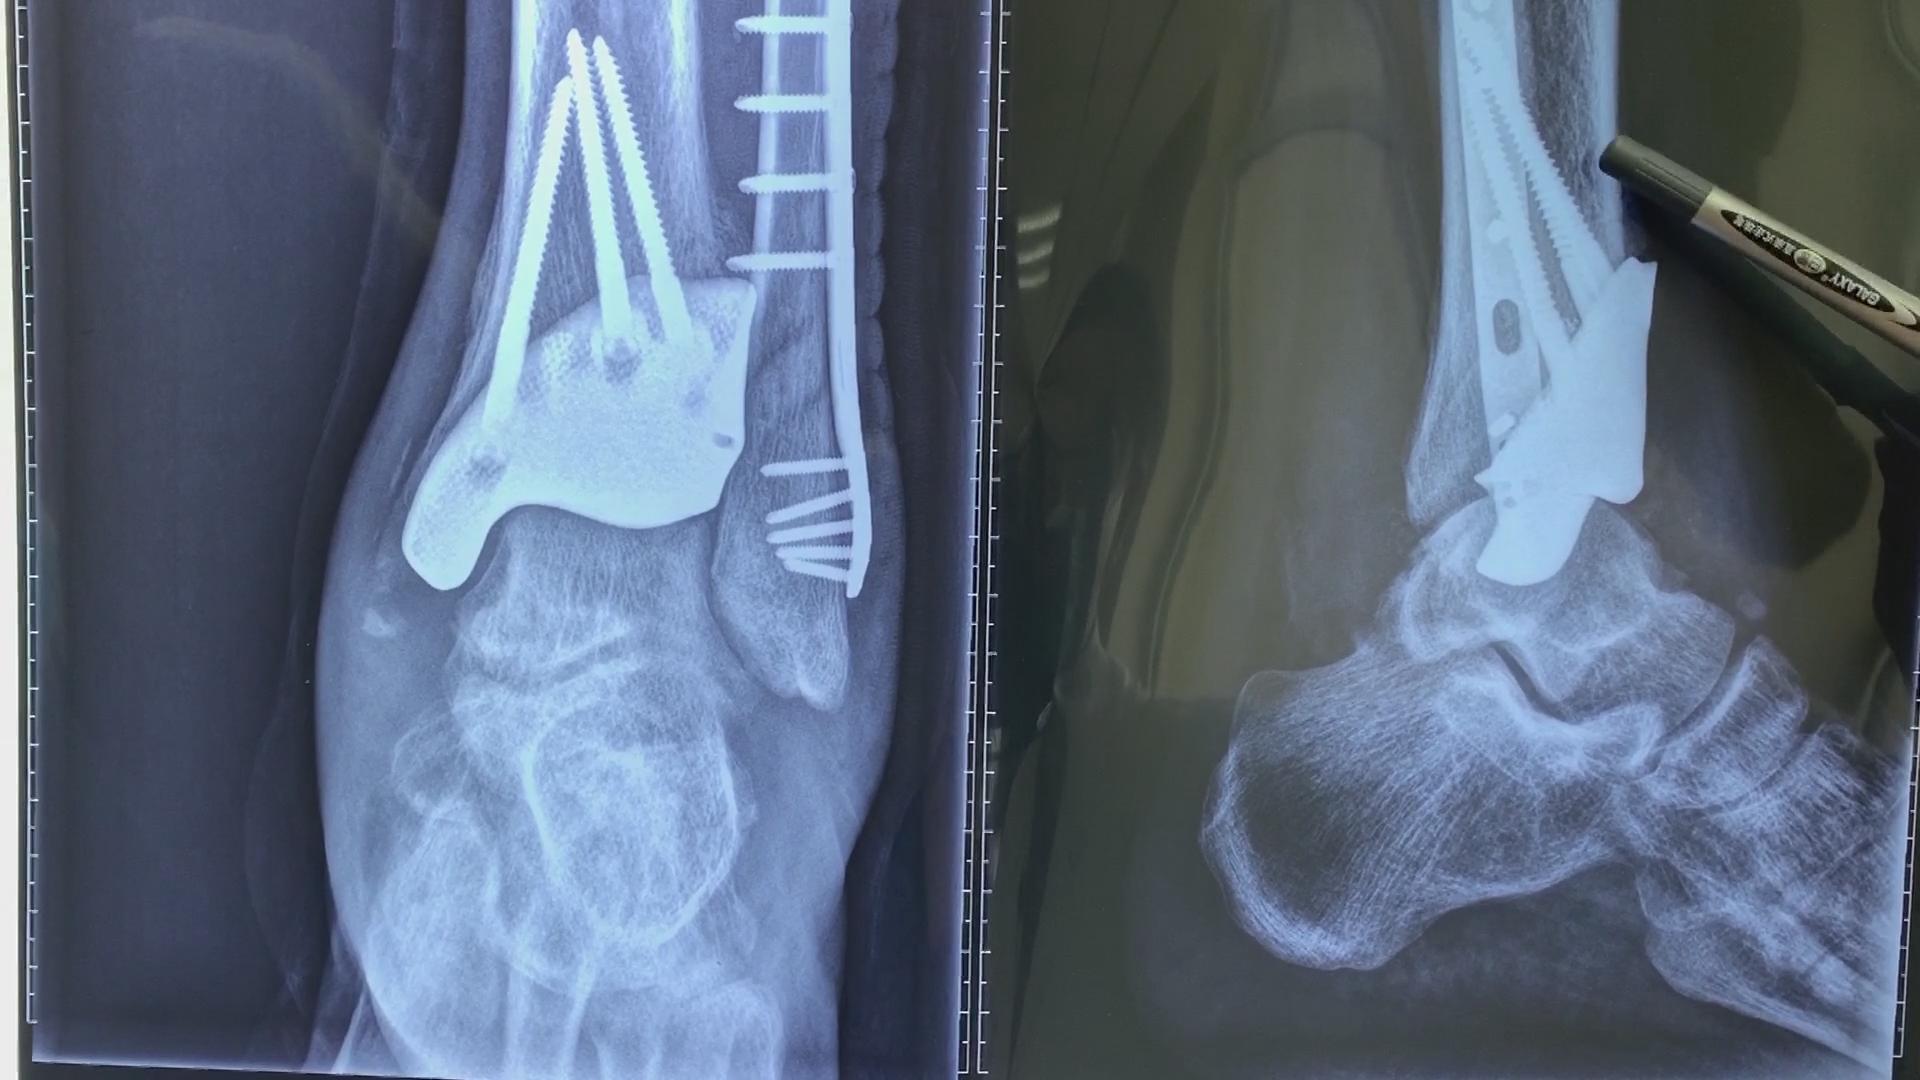

挺来挺去挺了半年,这时小刘的左脚已严重畸形,他这才在家人的劝说下去了医院。医生拍片一看大吃一惊,小刘原来的脚踝骨的小裂纹已经碎成了20多块,现在已经畸形愈合。这样的病例他们从来都没见过,要治疗只能把愈合的位置再次敲断,因为小刘的骨头损坏太严重,不能复位,只能做融合手术。

所谓融合手术,就是要从小刘身上再取块骨头填补到断处直接“焊上”,这样小刘的踝关节就不能打弯了,将会是终生残疾。小刘一听这不行呀,那自己不成瘸子了嘛!于是他不死心,走了沈阳好几家大型医疗机构,可医生给出的治疗建议都一样。

整个踝关节置换假体很容易做,可要是局部置换,还要做到严丝合缝,那绝对是私人定制,难度是相当大了。医生先根据小刘的好脚做出一个3D模型,再跟坏脚比对,一点点喷涂,才把需要置换的假体做出来。最终手术很成功,医生说小刘以后正常生活没啥问题,但不能剧烈活动,踢球就更#老茂说足踝# 不可能了。

成功植入假体